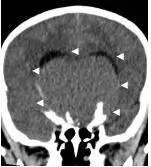

病例二:患儿女性,7岁,主因头痛2年,精神差1个月收入院。入院时头CT见典型的“超大型”颅咽管瘤,直径约9厘米,见图6。

图6.CT显示囊性颅咽管瘤

白色三角显示肿瘤边界